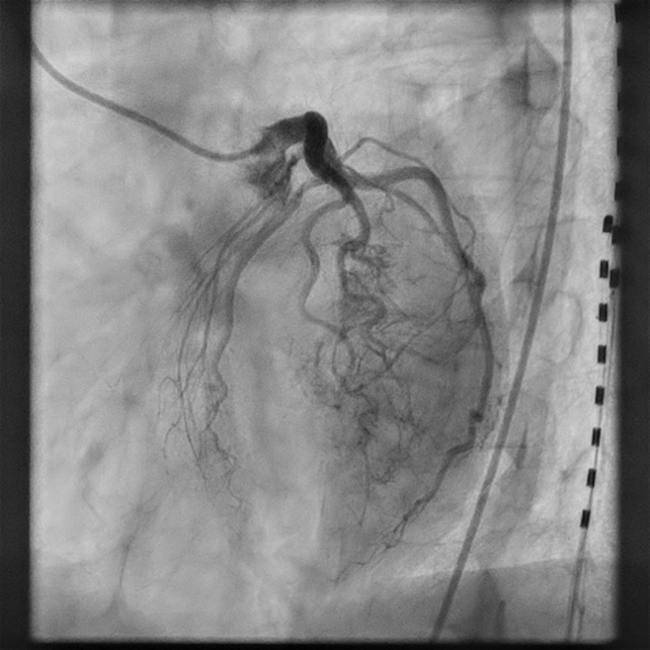

Thebesian Veins Causing Severe Myocardial Ischemia Due to Coronary Steal

Video 2. Stress-induced severe hypokinesis in the left anterior descending coronary artery territory.